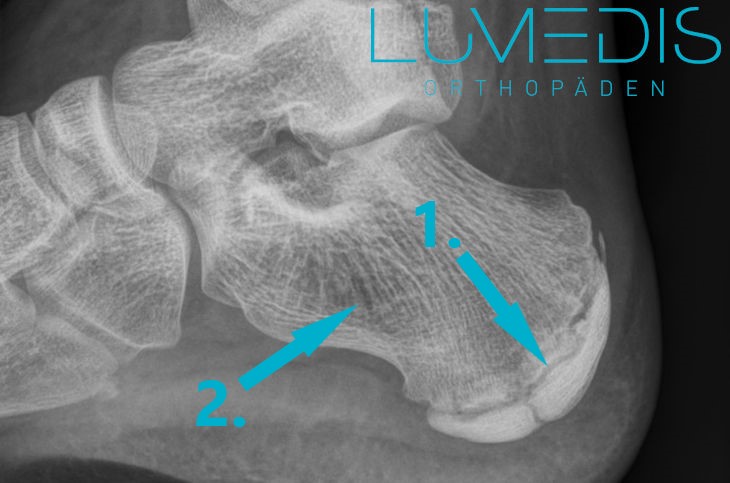

Röntgenbild einer Ferse seitlich:

Risiken für einen Fersensporn

Röntgenbild der Ferse seitlich:

Röntgenbild Ferse seitlich

Röntgenbild einer Ferse seitlich

Abbildung eines Röntgenbildes Ferse seitlich:

Weitere Informationen zu diesem Bild erhalten Sie unter unserem Artikel Fersensporn.